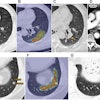

The radiologists conducted their interpretations using dedicated software (V3D Colon, Viatronix) with a 3D-2D hybrid approach for polyp detection, according to the report.